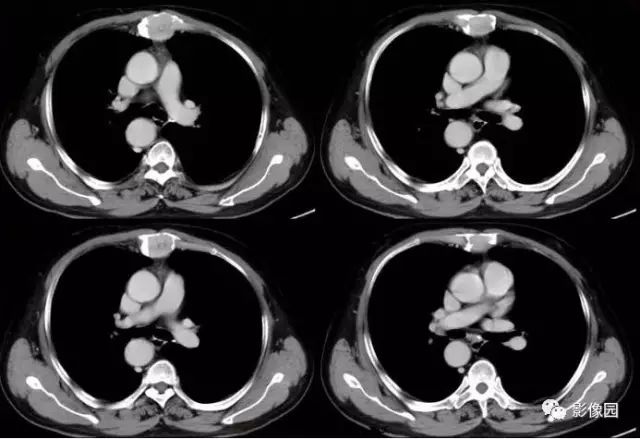

肚肚丫头: 胸骨体局部呈膨胀性骨质吸收破坏,内呈软组织密度影,可见点状钙化,增强扫描呈轻度强化,周围软组织略肿胀。考虑:1.骨巨细胞瘤;2.浆细胞瘤;3.嗜酸性肉芽肿

CT表现:特征性穿凿状、鼠咬状及蜂窝状骨破坏,边缘清楚,骨质疏松,病理性骨折及软组织肿块等表现,骨质硬化及骨膜反应少见。

骨破坏区完全为软组织取代,骨质膨胀,边界清楚,常突破骨皮质形成软组织肿块。增强扫描可见病灶轻中度强化,一般于静脉期达峰值。